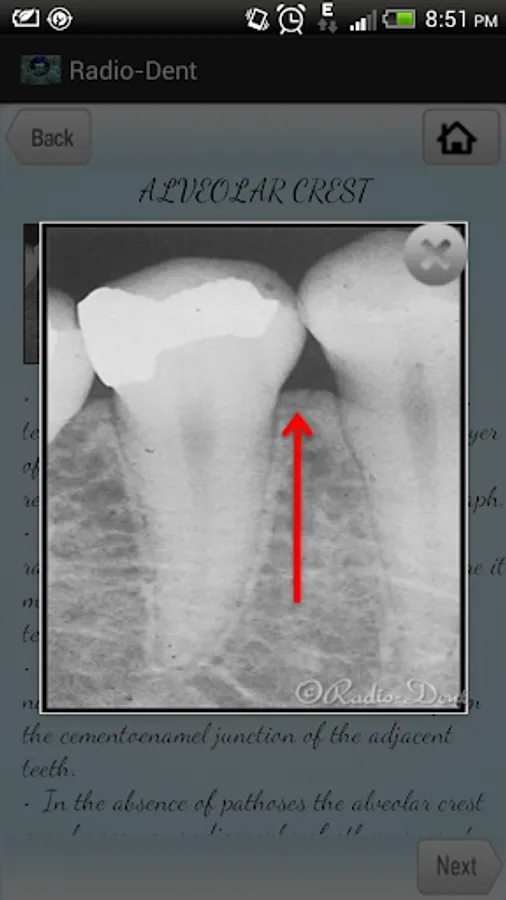

This is the first smart phone application in the field of dental radiology that can be easily and effectively used. We have compiled various radiographs for making students understand the subject easy and in an interesting way. The information provided is concise aiding to interpret a radiograph and diagnose the underlying condition. This app helps students learn and identify the normal anatomical land marks, common radiographic errors and pathologic conditions. This is a first step and this app will be regularly updated with new images in future.